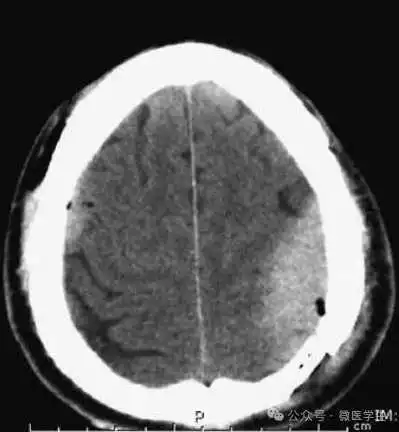

颅脑CT常用的三个窗(图A-C):

- 图B:脑窗(the brain window)

图B:脑窗;可清晰显示灰白质,可发现中风的早期征象或其他导致脑水肿等表现的病变。

本例表现:骨窗示:右顶骨骨折;三个窗均示:软组织水肿并皮下积气;血窗:少量硬膜下血肿。